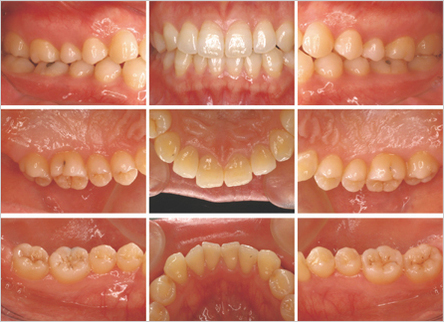

口腔内写真

歯の形態、噛み合わせ、詰め物の状態、歯茎の色、形などの現状をカラー写真で記録します。